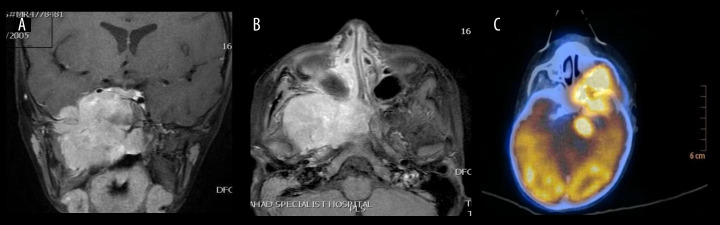

BACKGROUND Pediatric sinonasal tumors are rare, accounting for about 4% of all pediatric head and neck neoplasms. Due to their nonspecific symptoms such as nasal obstruction, epistaxis, and facial pain, these tumors often present diagnostic challenges and lead to delays in managment. Early and accurate diagnosis is crucial to optimize clinical outcomes. CASE REPORT This is a retrospective review of 4 pediatric patients with diagnosis of sinonasal tumors at a tertiary hospital in Saudi Arabia. The series includes 2 benign tumors, osteoma and juvenile nasopharyngeal angiofibroma, and 2 malignant tumors, NK/T-cell lymphoma and rhabdomyosarcoma. Diagnostic workups included nasal endoscopy, CT, MRI, and PET-CT imaging, followed by histopathological confirmation. Benign tumors were successfully treated with image-guided endoscopic excision, with no evidence of recurrence during follow-up periods of 2 and 5 years, respectively, while malignant tumors required a multimodal approach, combining chemotherapy and radiotherapy under multidisciplinary care, and showed stabilization after treatment with continued surveillance. The variety in presentation and complexity of management underscore the diagnostic and therapeutic challenges in this population. CONCLUSIONS This case series highlights the importance of early suspicion, comprehensive imaging, and individualized treatment plans in managing pediatric sinonasal tumors. The use of minimally invasive surgical techniques and preoperative embolization was effective in selected cases. The findings emphasize the role of multidisciplinary collaboration in optimizing outcomes for benign and malignant tumors. Future research should aim to develop standardized diagnostic algorithms and explore advanced diagnostic tools, such as molecular imaging, to facilitate earlier detection and improve treatment precision in pediatric sinonasal oncology.